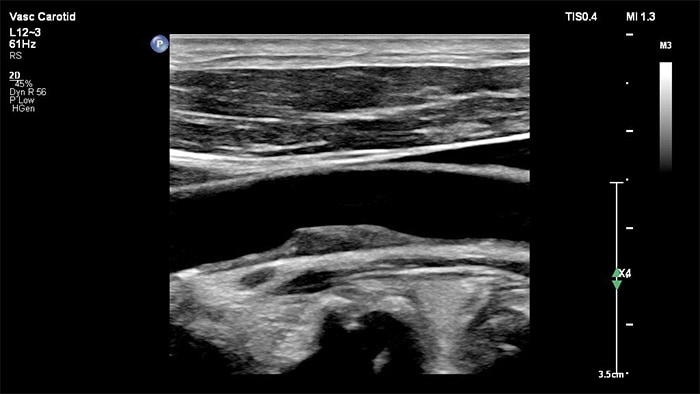

Imágenes xPlane

El transductor XL14-3 xMATRIX ofrece una adquisición de imágenes xPlane que supera al sistema convencional para exploraciones vasculares, pues ofrece imágenes en tiempo real tanto en los planos longitudinal como transversal de forma simultánea. La ventaja principal: las imágenes xPlane eliminan la necesidad de girar el transductor para adquirir vistas ortogonales. Basta con mover la esfera para realizar una evaluación anatómica completa, con lo que se ahorra tiempo en la exploración.